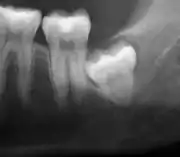

| Diagnostic method | Examination, x-ray |

Impacted wisdom teeth are classified by their direction of impaction, their depth compared to the biting surface of adjacent teeth and the amount of the tooth's crown that extends through gum tissue or bone. Impacted wisdom teeth can also be classified by the presence or absence of symptoms and disease. Screening for the presence of wisdom teeth often begins in late adolescence when a partially developed tooth may become impacted. Screening commonly includes a clinical examination as well as x-rays such as panoramic radiographs.

If the tooth cannot be assessed with clinical exam alone, the diagnosis is made using either a panoramic radiograph or cone-beam CT. Where unerupted wisdom teeth still have eruption potential several predictors are used to determine the chance of the teeth becoming impacted. The ratio of space between the tooth crown length and the amount of space available, the angle of the teeth compared to the other teeth are the two most commonly used predictors, with the space ratio being the most accurate. Despite the capacity for movement into early adulthood, the likelihood that the tooth will become impacted can be predicted when the ratio of space available to the length of the crown of the tooth is under 1.[5]: 141